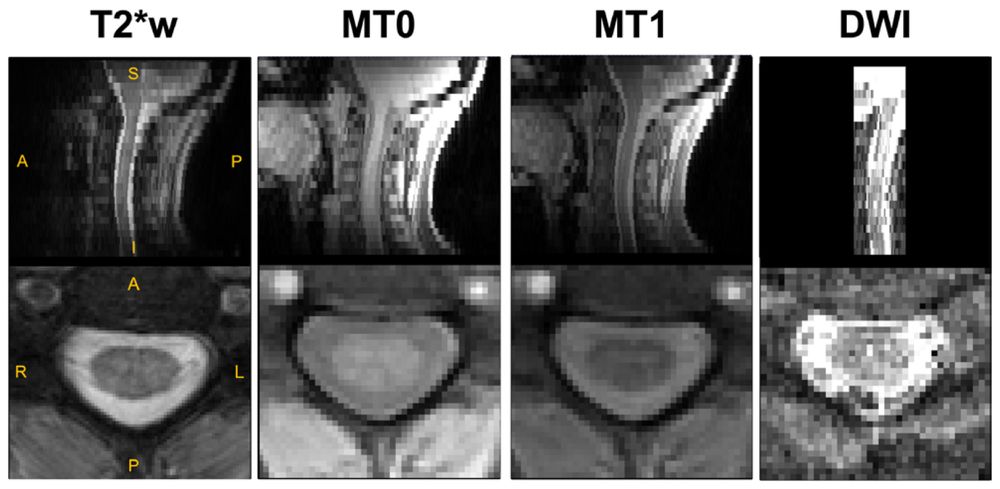

Parkinson’s disease in the spinal cord: An exploratory study to establish T2*w, MTR and diffusion-weighted imaging metric values

doi.org/10.1162/IMAG...

Parkinson’s disease in the spinal cord: An exploratory study to establish T2*w, MTR and diffusion-weighted imaging metric values

doi.org/10.1162/IMAG...